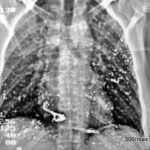

Bild 10: Diagnose? Warum ist es schwierig oder unmöglich, diese Pathologie in der Summationsradiografie (im üblichen Röntgenbild) zu beobachten?

Beidseitig verkalkter Fibrothorax in der dorso-medialen Pleura. – Die Verkalkung wird im Standardröntgenbild (posterior-anterior) nicht tangential projiziert und daher übersehen. (Eine kleine Verkalkung auf der rechten lateralen Seite ist nur bei sehr sorgfältiger Beobachtung erkennbar).